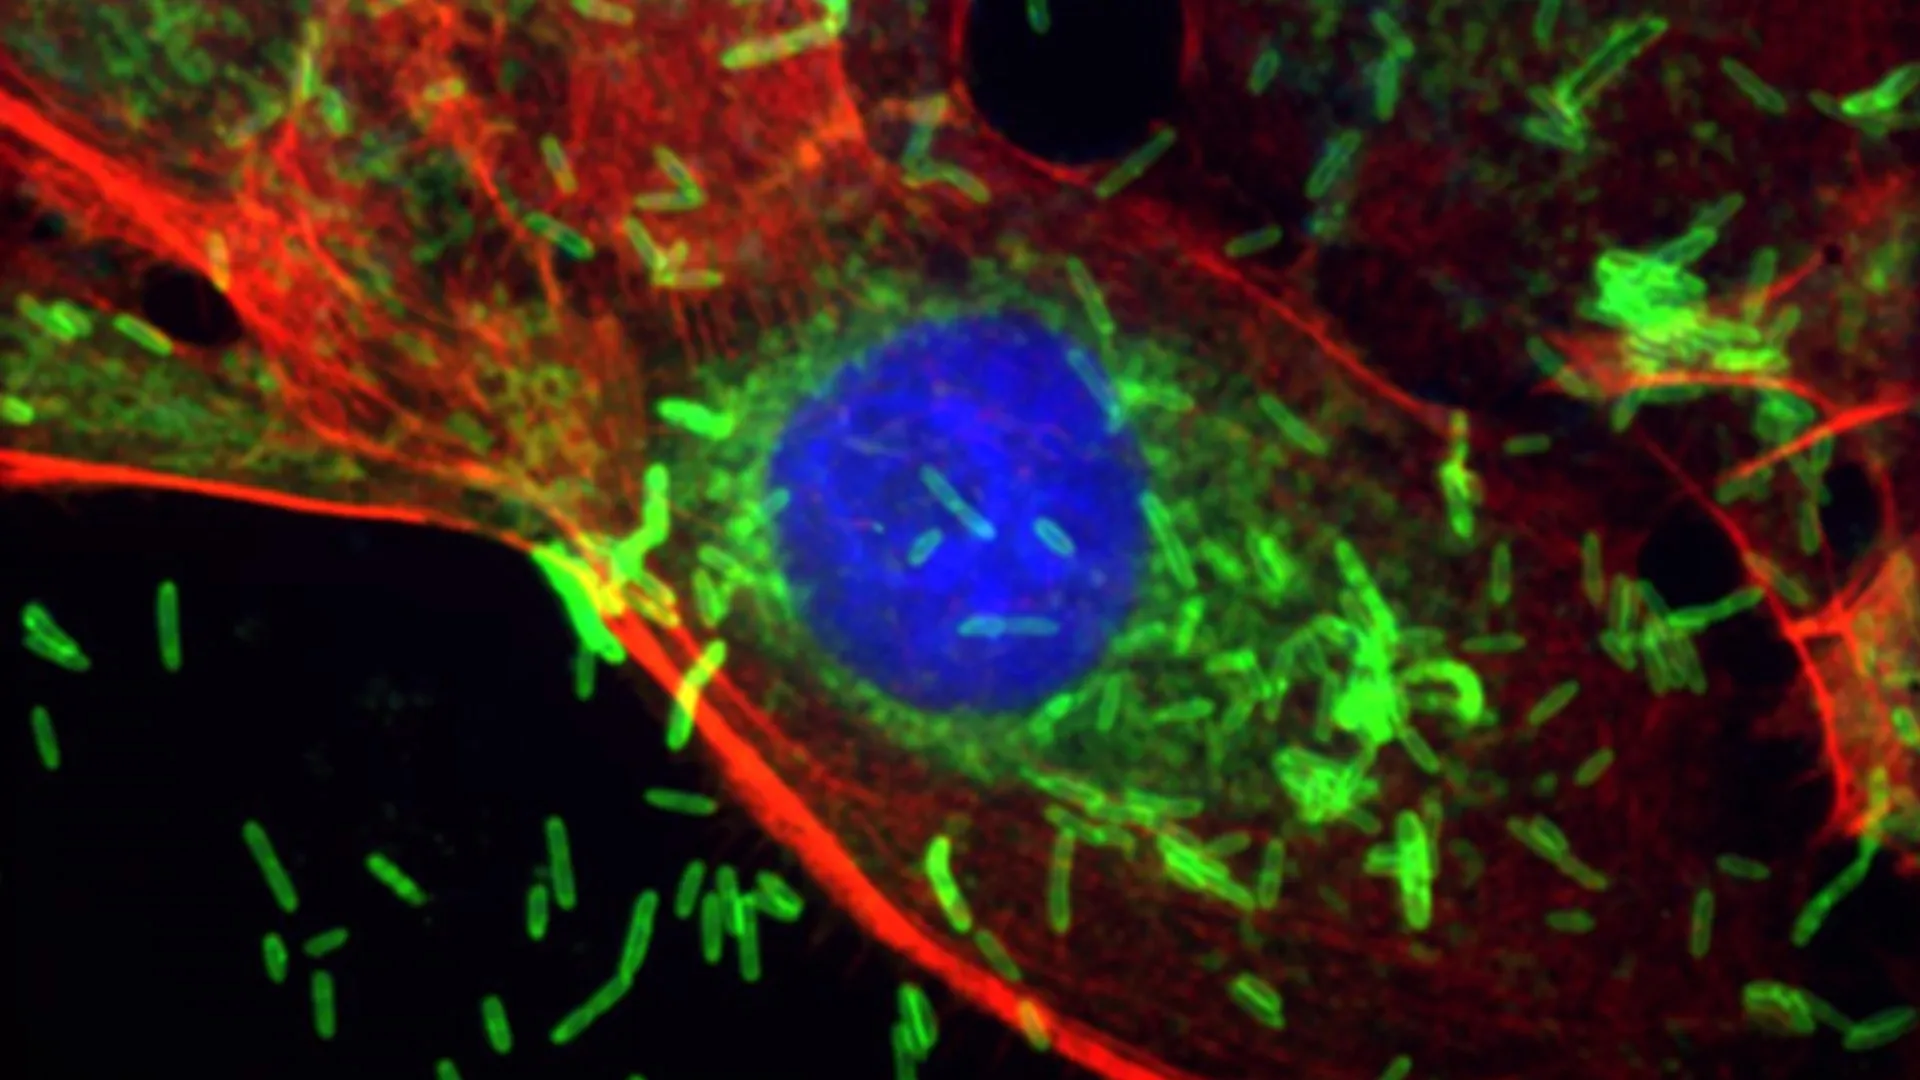

Periodontal Pathogen Identified as Novel Driver in Breast Oncogenesis and Metastasis

Pioneering research from the Johns Hopkins Kimmel Cancer Center and the Bloomberg~Kimmel Institute for Cancer Immunotherapy has unearthed a profound and previously underappreciated connection between oral microbial ecology and mammary…